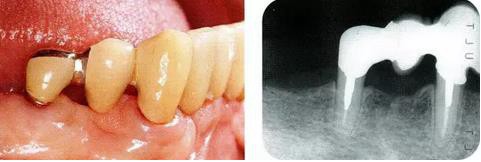

圖17-1 ( 左 ),2  ( 右 ) ▲  右下4近中9mm的骨緣下缺損,兩側(cè)全口橋體修復(fù),但是這顆患牙保留的情況下會(huì)影響牙列的維持,鄰接牙的骨水平在較高的位置,拔牙后可以獲得平坦的骨水平。即使是右下4嘗試再生療法,假說(shuō)可以100%的成功,右下3遠(yuǎn)中骨水平也會(huì)形成3mm以上的臺(tái)階。而且再生治療也需要患者登上1年半以上的時(shí)間。所以最終選擇拔牙的處理。